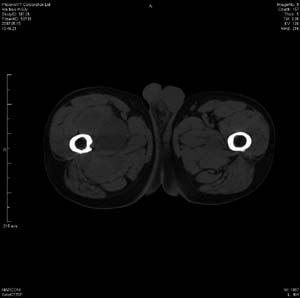

男 63岁 右大腿无痛性肿块11年,x片右大腿软组织肿块影,余无明显异常.ct值-13__239hu

右大腿股内侧股与收肌间隙间多发囊实性占位,界清.内示斑点状钙化.局部骨质无异常.肌肉推压移位表现.

考虑肌间隙病变.可有1,神经来源肿瘤.2,血管来源病变.3,淋巴来源肿瘤.4,脂肪来源肿瘤.5,滑膜来源肿瘤.结合病史只能考虑良性占位.建议增强或mri进一步分析.

同意,病史较长,病变周围分界清晰,考虑良性病变。病灶内有多发斑点状钙化,沿肌间隙生长,血管瘤或淋巴管瘤首先考虑。